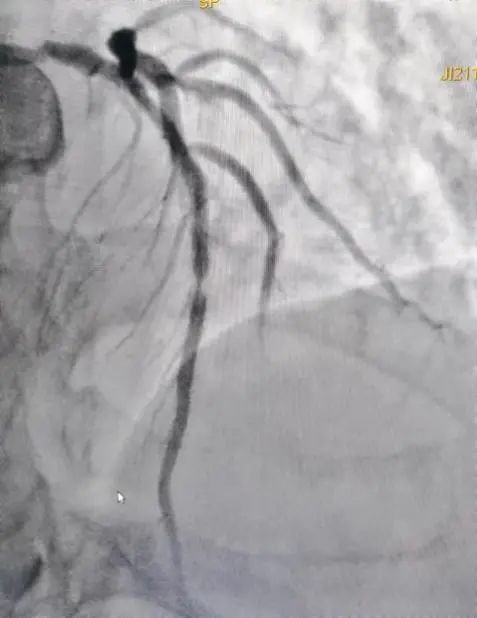

如川崎病引起的血管炎症导致血管狭窄,如图为一位20岁川崎病人的右冠状动脉,近段有一处非常狭窄,考虑到病人年纪尚青,血管炎症又会影响支架的植入,选择用药物球囊治疗,术中用ivus测量了病变处管腔的狭窄程度和长度,选择了适合的药物球囊,术后造影可以看出病变处狭窄明显改善,达到治疗目的。